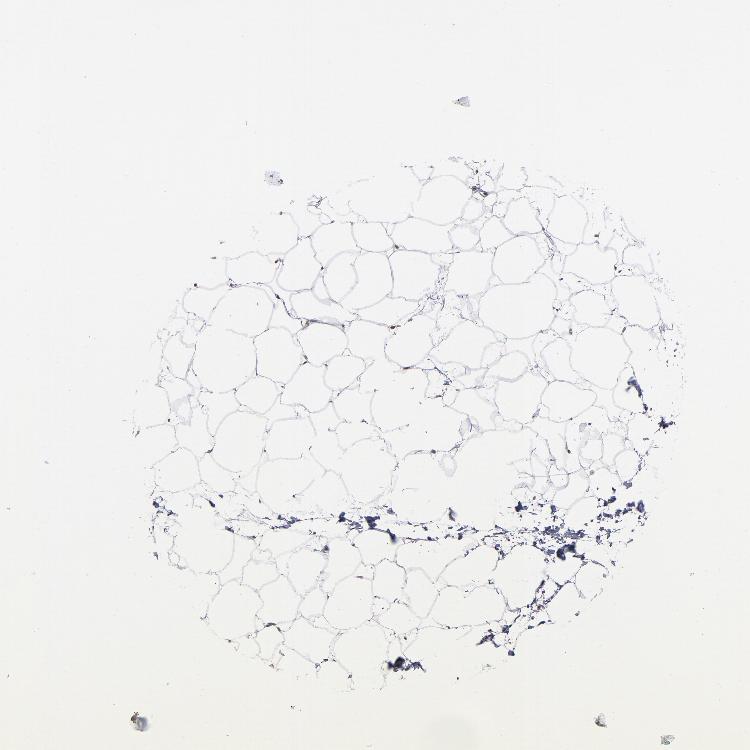

ADIPOSE TISSUE - Antibody stainingi

Antibody staining in the annotated cell types in the current human tissue is reported as not detected, low, medium, or high, based on conventional immunohistochemistry profiling in selected tissues. This score is based on the combination of the staining intensity and fraction of stained cells.

Each image is clickable and will lead to virtual microscopy that enables deeper exploration of all samples and also displays staining intensity scores, fraction scores and subcellular localization as well as patient and tissue information for each sample.

Antibody HPA002548Antibody CAB022718

Adipocytes Not detectedLow